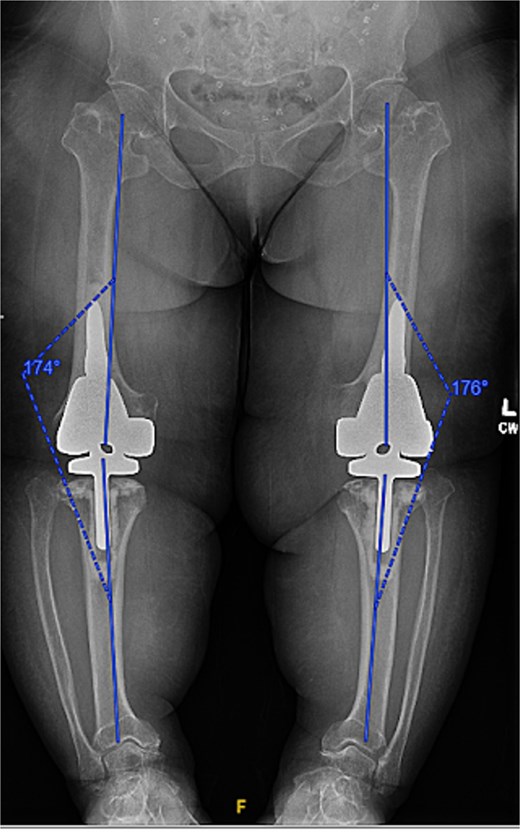

A 61-year-old woman with a history of achondroplasia, gastroesophageal reflux disease, depression, and sciatica presented with progressively worsening bilateral knee pain, mechanical symptoms, and significant difficulty with ambulation. The patient had a body mass index (BMI) of 41.1 kg/m2 and a characteristic short-limb SD phenotype consistent with achondroplasia. On physical examination, the patient demonstrated bilateral varus alignment of the lower extremities and gait assessment revealed a significant varus thrust and valgus instability in mid-stance. Bone length radiographs revealed severe medial joint space narrowing, metaphyseal flaring of the tibia and femur, and bilateral mechanical axis varus deformity measuring 36 and 44 degrees on the left and right legs, respectively (Fig. 1).

Preoperative standing AP radiographs demonstrating severe bilateral mechanical axis varus deformity measuring 36 and 44 degrees on the left and right legs, respectively.